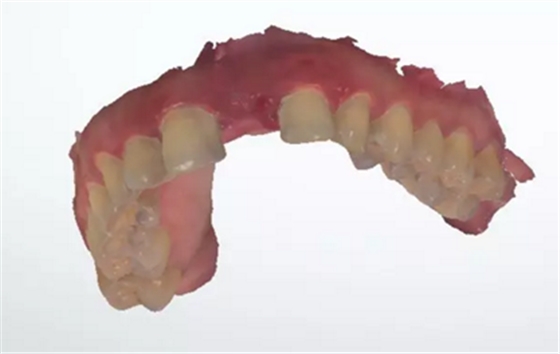

術(shù)前檢查

1.術(shù)前CT

2.術(shù)前植體設(shè)計(jì)